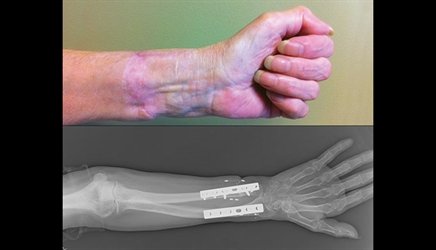

Replantation surgery involves the reattachment of a severed body part, such as a finger, hand, or limb, using advanced microsurgical techniques. This complex procedure is often time-sensitive and aims to restore both function and appearance.